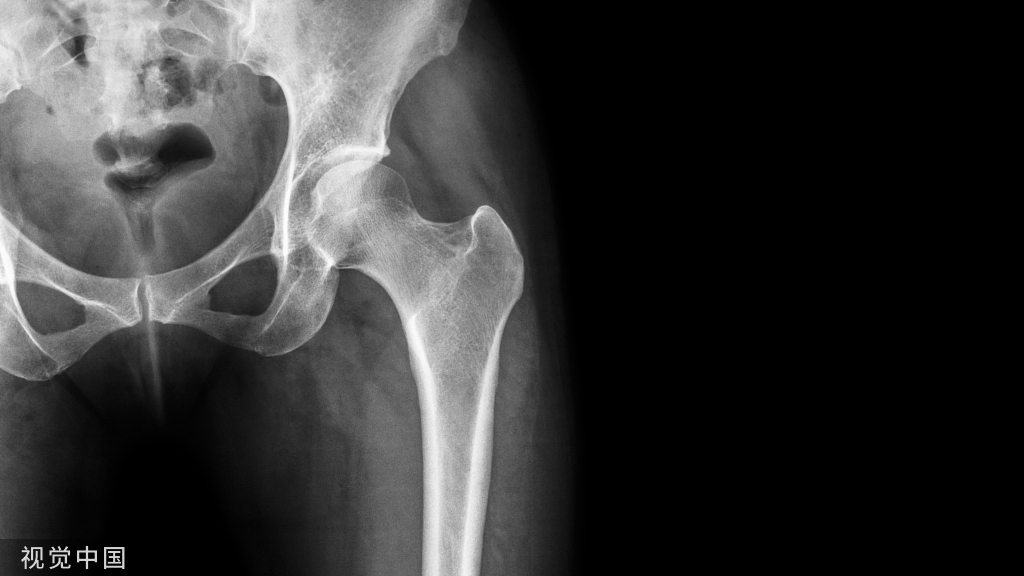

②  男性骨质疏松性骨折: 来自美国华盛顿大学 Gage 研究团队的一项回顾性研究显示, 长期服用华法林的男性房颤患者 , 发生骨质疏松性骨折的危险增加 。

结果发现,长期使用华法林发生骨质疏松性骨折的危险比未用华法林者高 25%,且这种仅限于男性,在女性中并不存在。除此之外,短期(<1 年)使用者并不增加骨质疏松性骨折的危险。

进一步分析显示,骨质疏松性骨折的独立危险因素包括年龄较大、易跌倒、合并有甲亢及神经衰弱疾病和酗酒。而非洲裔和 β 受体拮抗剂的使用则可降低骨折危险。